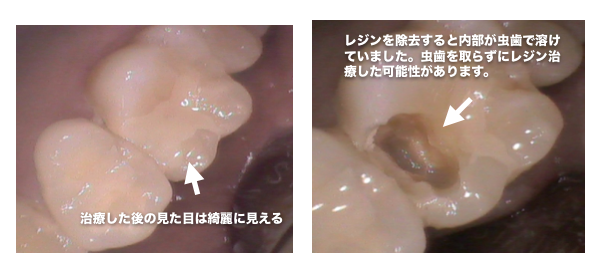

以前治療したレジン治療の内部から虫歯の取り残しが見つかった症例

レジン治療の内部で虫歯の取り残しがあった症例